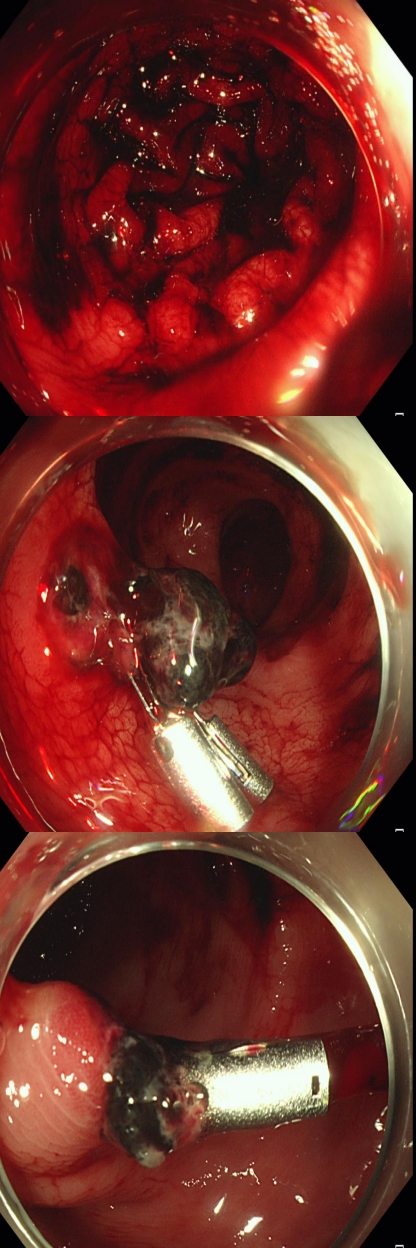

姚某,男,距肛65cm、乙状结肠、直肠可见多枚直径约0.1-1.5cm的广基息肉、扁平及亚蒂、长蒂息肉,给予内镜下行息肉高频电切除术,钛夹夹闭创面。

患者手术后住院治疗,住院期间由于没有遵循医嘱,进行高强度活动后出现大量便血,再次给予内镜下止血治疗。

(行内镜下止血治疗)

3、再次肠镜下止血治疗;